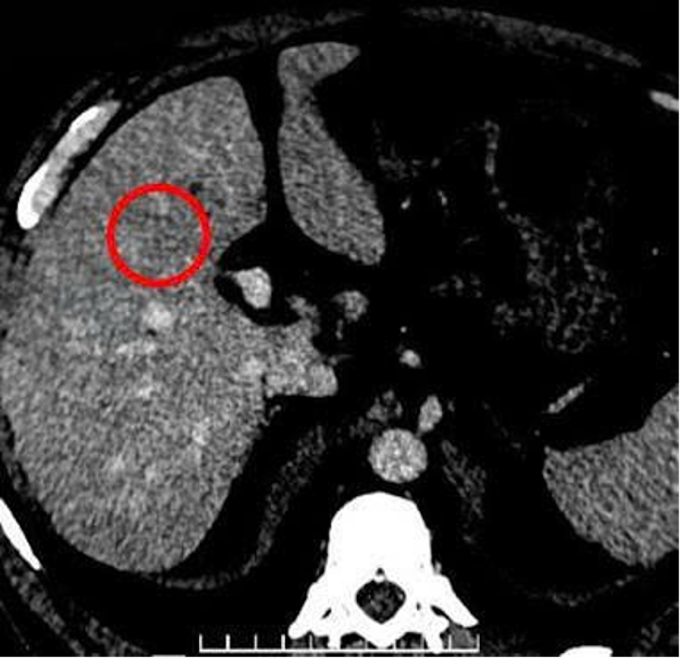

Gần đây, ông thường xuyên mệt mỏi, ăn uống kém, đau âm ỉ vùng hạ sườn phải, đến Bệnh viện Đa khoa Tâm Anh TP HCM khám. Chụp cắt lớp vi tính (CT) cho thấy tại phân thùy 4 của gan có một khối tổn thương giảm đậm độ, kích thước khoảng 22x24 mm, tăng quang rõ ở thì động mạch. Tại các hạ phân thùy 6 và 7 còn ghi nhận thêm một vài nốt nhỏ kích thước khoảng 5 mm. Sinh thiết gan dưới hướng dẫn siêu âm cho kết quả ung thư biểu mô tế bào gan (hepatocellular carcinoma - HCC) ở giai đoạn sớm.